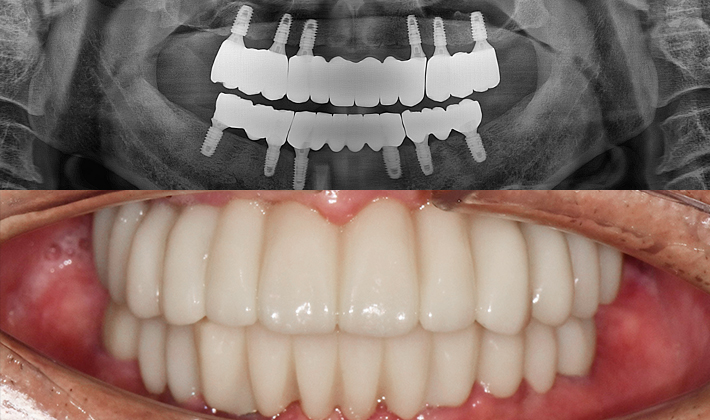

before

after

※ 위 임상사진은 동일조건으로 촬영되었으며, 사진에 대한 별도의 조작이 처리되지 않았습니다.

※ 위 임상사진 및 포트레이트는 환자와의 포괄적인 초상권 계약 이후 사용하고 있습니다.

※ 수술 및 치료과정에서 부작용이 발생할 수 있으므로 충분한 상담과 신중한 판단이 요구됩니다.

실제 치료 사례

수많은 환자들이 고민 끝에 선택한 치료,

그리고 그 후의 놀라운 변화

- ※ 위 임상사진은 365서울원탑치과에서 진료를 시작하고 마친 동일한 환자의 사진입니다.

- ※ 위 임상사진은 동일한 장소에서 동일한 조건으로 촬영되었으며, 사진에 대한 별도의 조작이 처리되지 않았습니다.

- ※ 수술 및 치료 과정에서 부작용이 발생할 수 있으므로 의료진과의 충분한 상담과 신중한 판단이 요구됩니다.